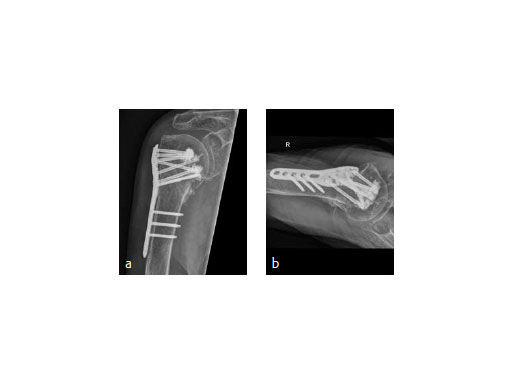

An 82-year-old male patient presented with a fracture dislocation of his right proximal humerus after a fall at home. Examinations revealed a highly unstable valgus-displaced 4-part fracture of the proximal humerus with a disruption of the medial hinge. No neurological injuries were evident (Fig 5).

The patient was placed in supine position, having the shoulder on two shoulder supports. After closed reduction of the shoulder, ORIF was performed via an anterior deltopectoral approach using the PHILOS. Four screws were augmented with Traumacem V+ under fluoroscopic control. Initially the treated shoulder was immobilized in a sling for 2 days followed by a pain-adapted functional treatment (Fig 6).

The X-ray review at 3 months after surgery showed an anatomic reduction of the fracture, nicely formatted augmentation, no secondary loss of reduction, and range of motion of the arm reaching the horizontal plane (Fig 7).